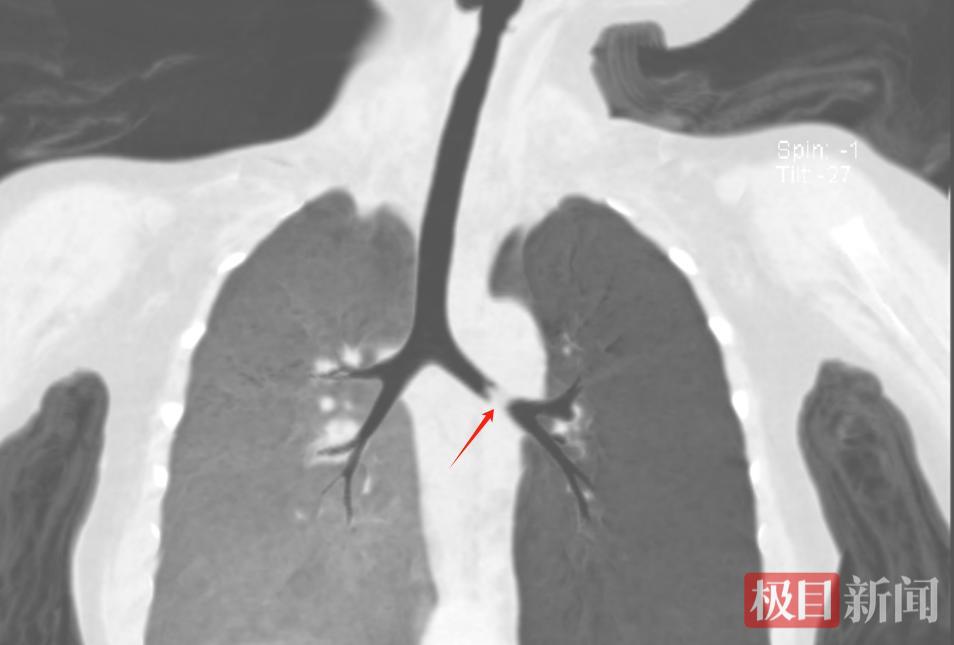

该院门诊以“急性喘息性支气管炎、支气管异物”将瑞瑞收入院。复查肺部CT提示,异物卡在了左侧支气管。情况紧急,该院耳鼻咽喉科医生迅速为其进行了全麻下气管镜支气管异物取出术。

堵在气道里的异物

孩子因为气道被异物堵塞,造成呼吸道梗阻。术中,专家需要经口行气管镜检查,这一操作有可能加重堵塞,因此手术对麻醉、手术医生救治能力要求很高。在耳鼻咽喉科、麻醉科、手术室团队协作下,有惊无险地取出了一块坚果。